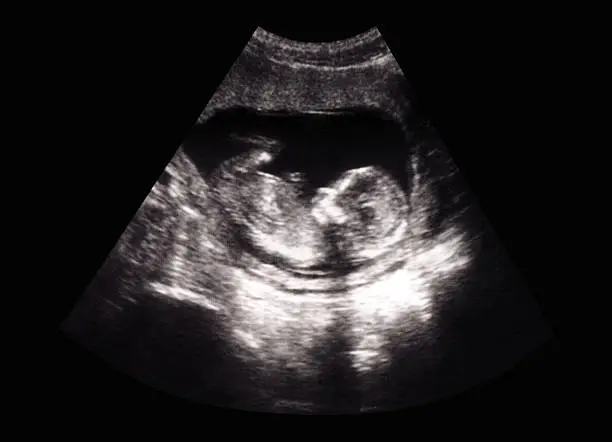

착상혈을 경험한 여성들은 보통 생리인지 임신 초기 증상인지 혼란스러울 수 있습니다. 이러한 경우 가장 중요한 것은 본인의 몸 상태를 잘 파악하는 것입니다. 착상혈이 나타나고 출혈이 멈춘 후에도 의심이 든다면, 임신 테스트를 통해 임신 여부를 확인하는 것이 좋습니다. 임신 테스트는 착상혈이 발생한 후 약 일주일이 지나면 정확한 결과를 얻을 수 있습니다.

또한 착상혈 외에도 임신 초기에는 피로감, 가슴 통증, 소화불량, 구토 등의 증상이 동반될 수 있으므로 이러한 징후들을 함께 고려하여 임신 가능성을 판단할 수 있습니다. 착상혈이 생리와 다르다고 느껴지면 당황하지 말고 차분히 몸의 신호를 읽는 것이 중요합니다. 경우에 따라 착상혈이 나타나지 않는 여성도 있으니, 출혈 여부만으로 임신을 판단하기보다는 전체적인 신체 변화를 종합적으로 판단하는 것이 바람직합니다.